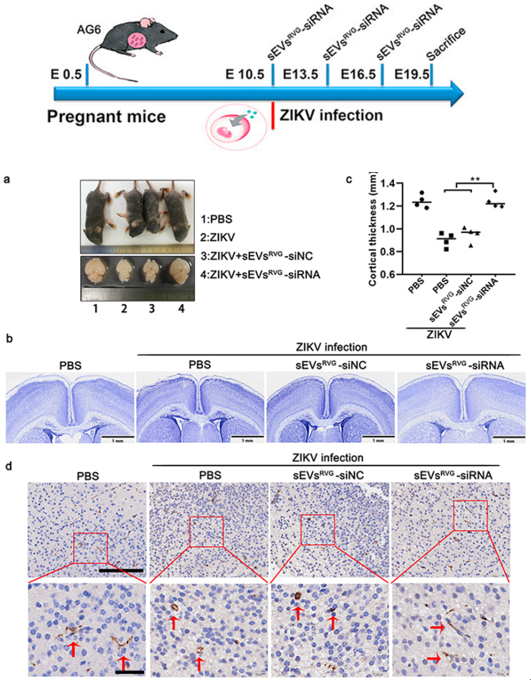

图5:sEVsRVG-siRNA保护胎鼠免受ZIKV感染并`缓解ZIKV引起神经炎症和的神经系统损伤

最后,研究人员通过用ZIKV感染怀孕AG6小鼠构建了胎鼠小头症模型,并在孕鼠攻毒0/3/6天后给予sEVsRVG-siRNA进行治疗,sEVsRVG-siRNA治疗组相对于其他组在孕鼠胎盘、子宫及胎鼠脑部有较为明显的抑制病毒作用;饲养胎鼠到一定天数后,对比发现治疗组胎鼠的小头畸形有明显缓解并且sEVsRVG-siRNA的治疗降低了病毒造成的神经损伤及炎症。 在未来,针对孕期病毒感染造成的胎儿脑部损伤,RVG修饰细胞外小囊泡装载抗病毒小分子靶向治疗或许是种潜在可能。该研究工作也引起了国外相关媒体的关注。